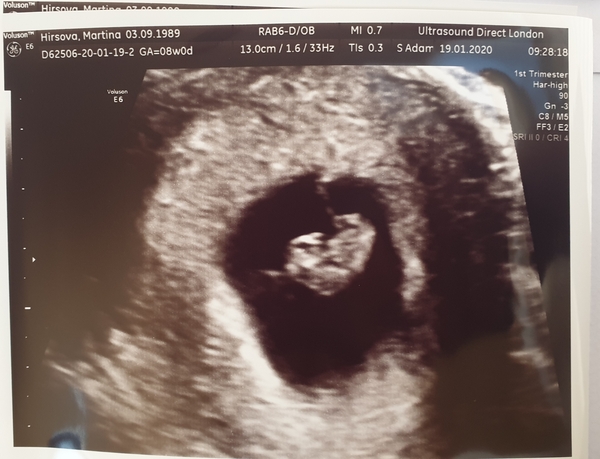

Martina2311 · 19/01/2020 11:25

I'm back home and everything is ok! Baby is exactly 8 weeks today and has a nice and regular heartbeat ❤❤❤ I was so emotional...I feel so relieved and so happy. At least I know now, that even if I don't feel pregnant at all, things are probably just fine. Hoping this reassurance will hold on to me for more than a couple of days this time. I've read somewhere that once you reach 8 weeks with a heartbeat, the risk of miscarriage is really rapidly dropping compared to the week 6 and 7. Still nothing is 100% but I feel much more positive. ❤

@Martina2311 we have exactly the same due date I also had my scan yesterday and they dated me at exactly 8 weeks found a nice heartbeat and said everything was fine such a relief isn’t it! I’m still symptomless but at least I now know it’s real x